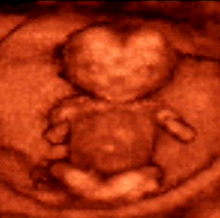

Kỹ thuật chẩn đoán hình ảnh là một chuyên ngành dùng các phương pháp tạo hình ảnh khác nhau để chẩn đoán bệnh bao gồm: kỹ thuật xquang chẩn đoán, siêu âm chẩn đoán, chụp cắt lớp vi tính, chụp cộng hưởng từ hạt nhân, xquang mạch máu và can thiệp. Siêu âm là kỹ thuật thăm khám đầu tay của các nhà chẩn đoán hình ảnh. Siêu âm Doppler cho phép đo được tốc độ dòng chảy trong mạch máu và buồng tim, được áp dụng rộng rãi để phát hiện các bệnh hẹp, tắc và dị dạng mạch máu ngoại biên và các tạng. Siêu âm 3D, 4D được ứng dụng rộng rãi trong sản khoa để nghiên cứu phát hiện sớm các dị tật thai nhi như dị tật đầu mặt, sọ não, cột sống, tim. Ngoài ra siêu âm 3D, 4D còn được ứng dụng trong nghiên cứu các khối u, đặc biệt là u tuyến giáp, tuyến vú.

Hình ảnh siêu âm 3D thai 15 tuần